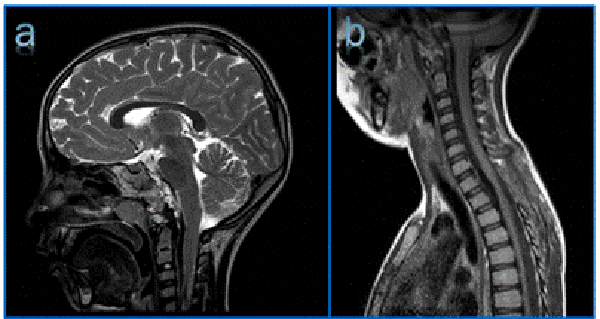

Se realiza una resonancia magnética de cerebro y columna donde se observan dos lesiones: una retroclival de gran tamaño, que comprime y desplaza el tronco encefálico, isointensa en T1, hiperintensa en T2 que realza homogéneamente con contraste; y una segunda lesión espinal, extradural, localizada entre T1-T3 que comprime y desplaza la médula hacia dorsal con las mismas características que la descripta previamente (Figura 1).

Figura 1: Resonancia magnética de cerebro y columna prequirúrgica donde se observan dos lesiones, una retroclival y otra dorsal anterior (T1-T3). a) Corte sagital en T1, lesiones isointensas con respecto al parénquima cerebral. b) Corte sagital en T2, lesiones hiperintensas. c) Corte sagital en T1 con contraste, realce homogéneo de ambas lesiones.

Figura 2: Resonancia magnética de cerebro y columna postoperatoria donde se observa la exéresis parcial de la lesión retroclival y la exéresis completa de la lesión T1-T3 a) Corte sagital en T1. B) Corte sagital en T2.